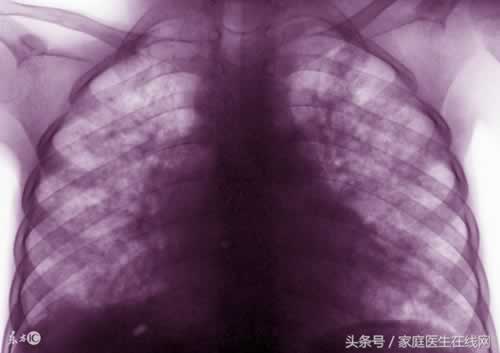

近日,湖南一中学发生群发性肺结核,弄得人心惶惶,也给很多学生造成了很大的伤害。那么肺结核有什么症状,我们又应该如何去预防?

肺结核有哪些症状?

1、咳嗽,乾咳或咳少量粘液痰。

2、咯血或痰中带血。

3、胸疼胸闷,气促、呼吸困难。

4、午后潮热、消瘦无力、食欲减退、盗汗、贫血、五心烦热等。